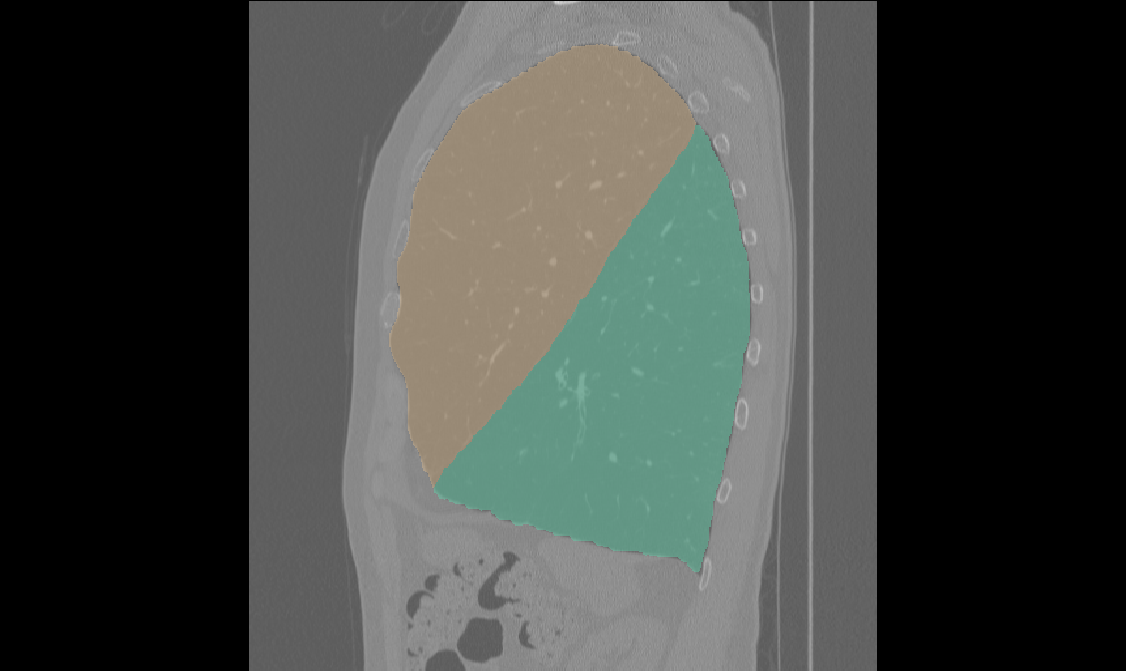

Edge-Aware 3D Image Segmentation Networks

[91]: Automated segmentation of kidneys and kidney tumors is an important step in quantifying the tumor’s morphometrical details to monitor the progression of the disease and accurately compare decisions regarding the kidney tumor treatment. Manual delineation techniques are often tedious, error-prone and require expert knowledge for creating unambiguous representation of kidneys and kidney tumors segmentation. We propose a 3D end-to-end edge-aware FCN for reliable kidney and kidney tumor semantic segmentation from arterial phase abdominal 3D CT scans. Our segmentation network consists of an encoder-decoder architecture that specifically accounts for organ and tumor semantics. We evaluate our model on the 2019 MICCAI KiTS Kidney Tumor Segmentation Challenge dataset. -

Furthermore, we extend our methodology and propose 3D boundary-aware FCNs for end-to-end and reliable semantic segmentation of kidneys and kidney tumor by encoding the information of edges in a dedicated stream that is supervised by edge-aware losses.

2 3D Edge-Aware Encoder-Decoders

1 Framework Architecture

As is illustrated in Figure 2, our network consists of the main segmentation branch and the additional boundary stream that processes the feature maps at the boundary level. The main branch, following [90], is an asymmetric encoder-decoder structure. The input to the encoder is a crop which is initially fed into a convolution with 16 filters. Feature maps are then extracted at each resolution by feeding them into a residual block followed by a strided convolution (for downsizing and doubling of the feature dimension).

The bottom of the encoder entails four consecutive residual blocks that are connected to the decoder. The extracted feature maps in the decoder are upsampled using bilinear interpolation and added with feature maps from the encoder. The output of the decoder is concatenated with the output of the boundary and fed into a convolution with 2 channels where channel-wise sigmoid activation determines the probability of each voxel belonging to kidneys and tumor or only tumor classes.